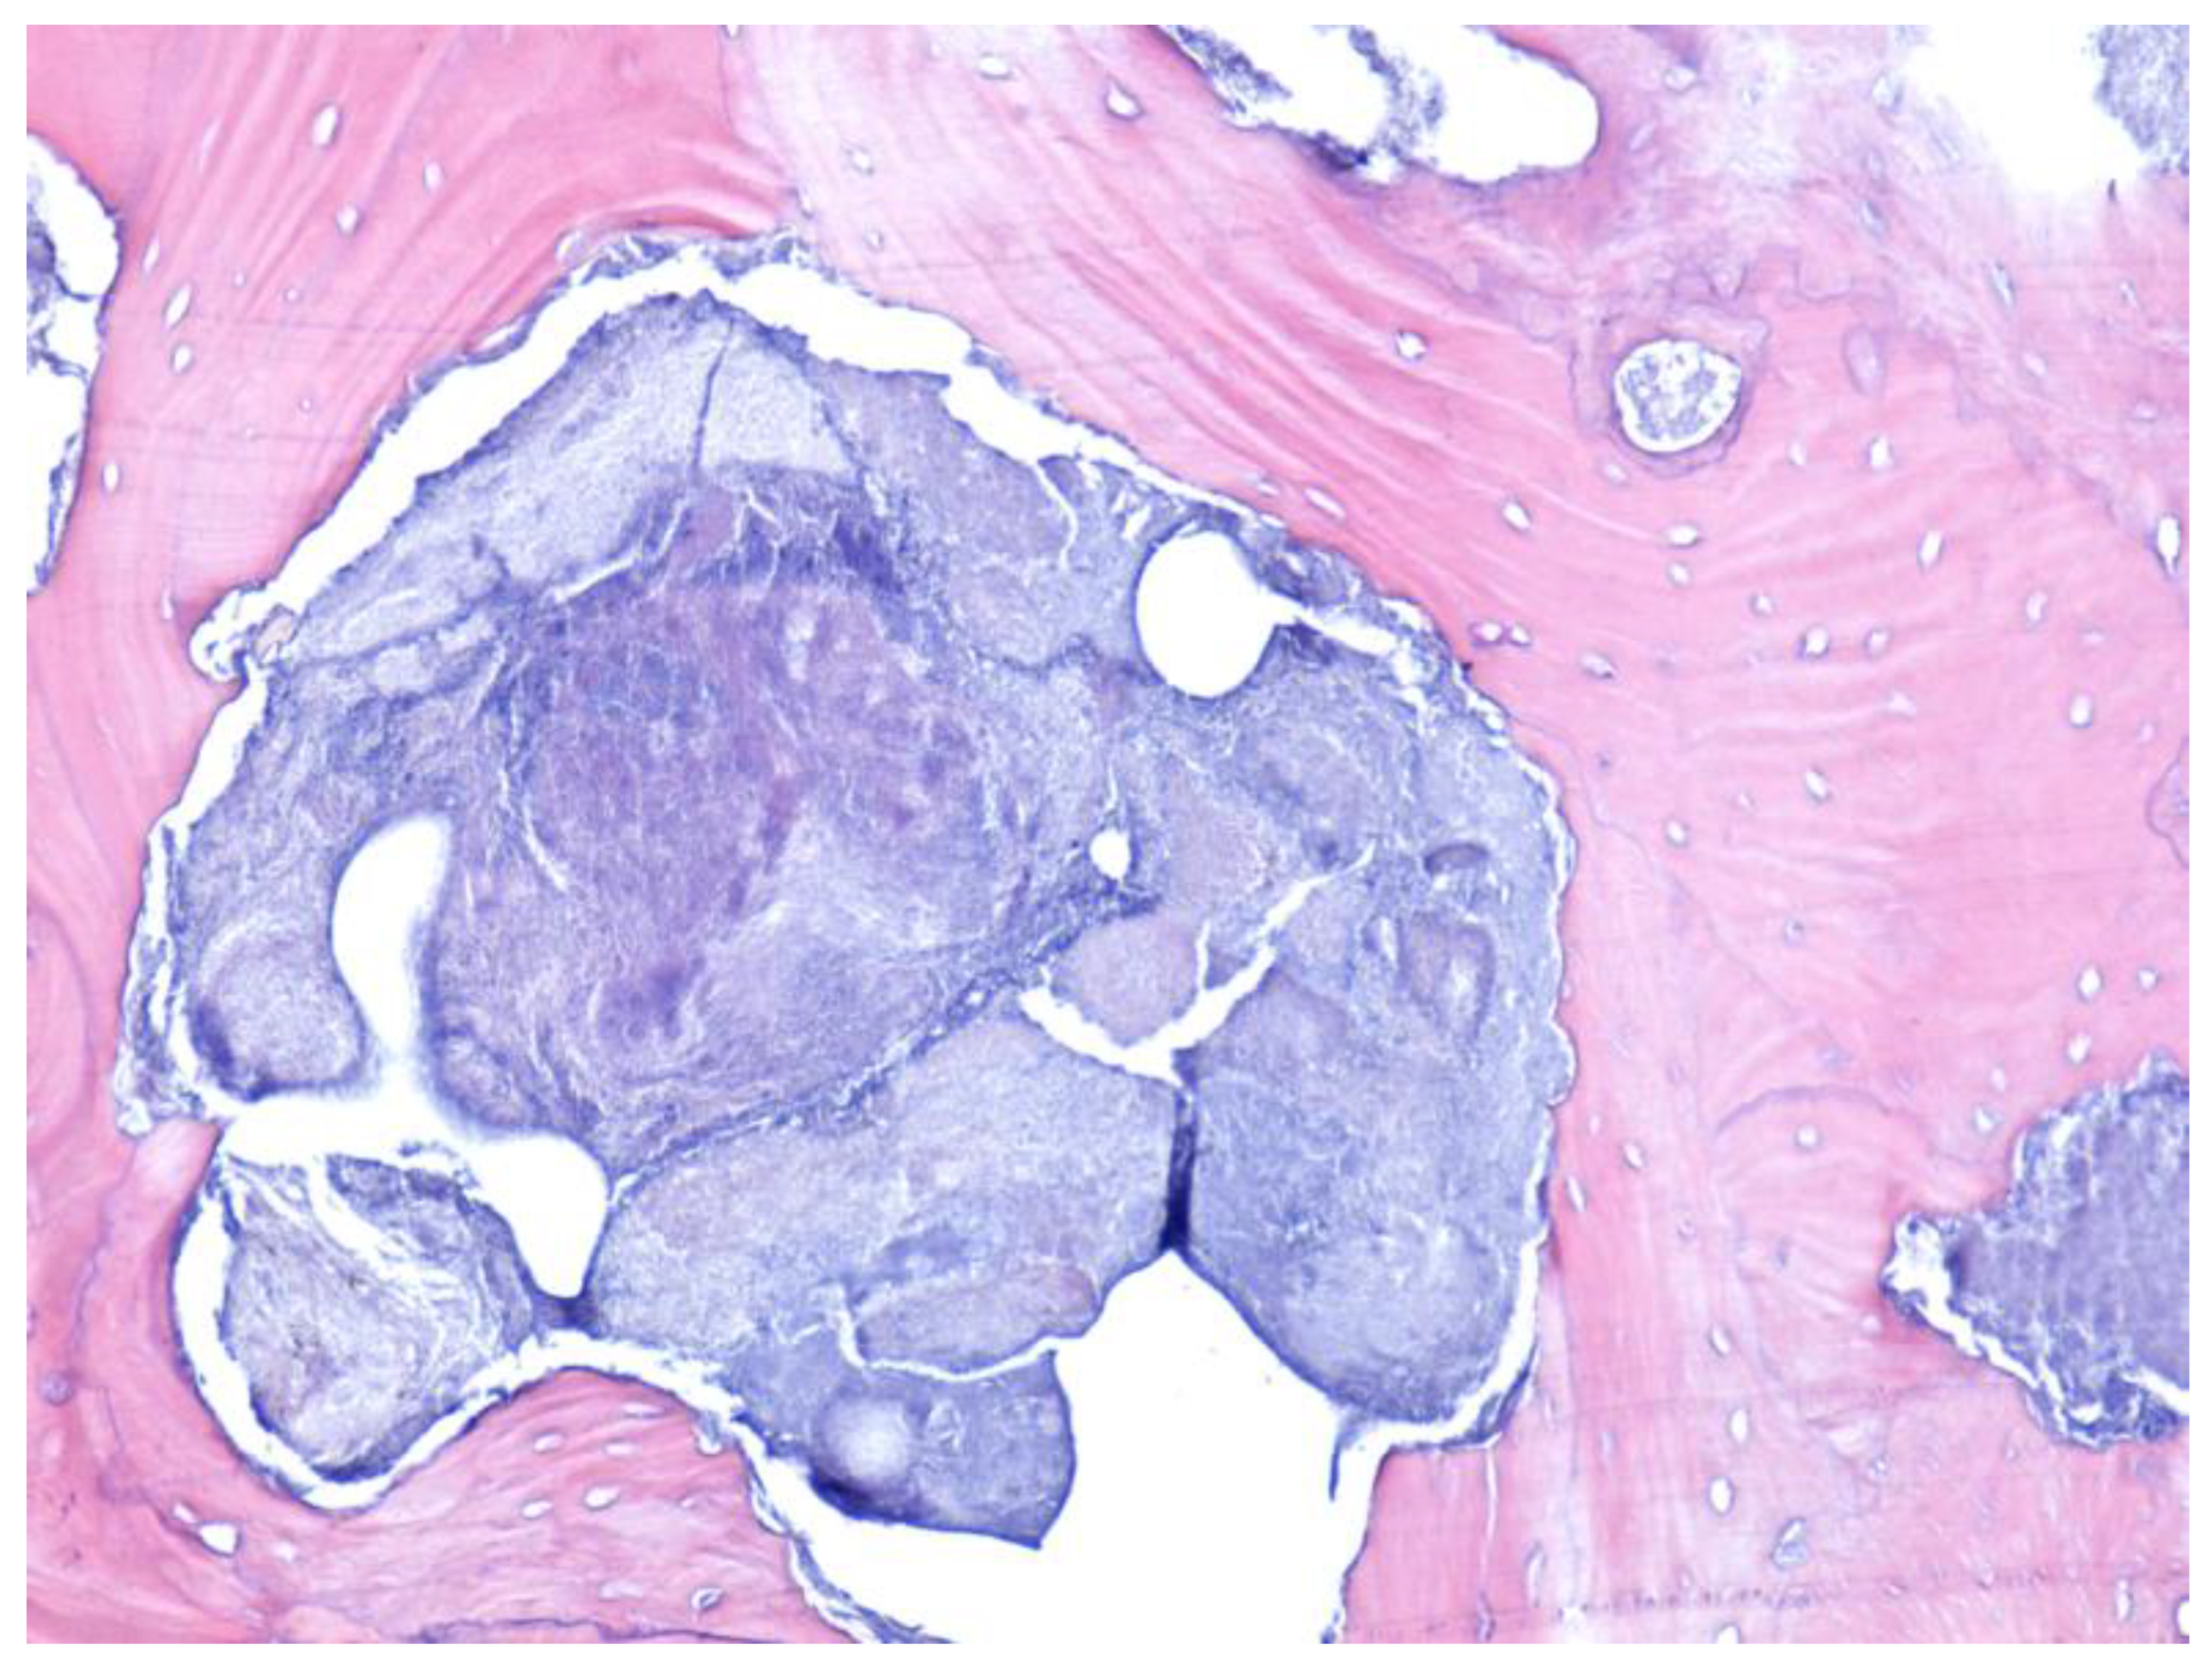

- Paparella, M.; Brandizzi, D.; Santini-Araujo, E.; Cabrini, R. Histopathological features of osteonecrosis of the jaw associated with bisphosphonates. Histopathology 2011, 60, 514–516. [Google Scholar] [CrossRef]

- Favia, G.; Pilolli, G.P.; Maiorano, E. Histologic and histomorphometric features of bisphosphonate-related osteonecrosis of the jaws: An analysis of 31 cases with confocal laser scanning microscopy. Bone 2009, 45, 406–413. [Google Scholar] [CrossRef] [PubMed]